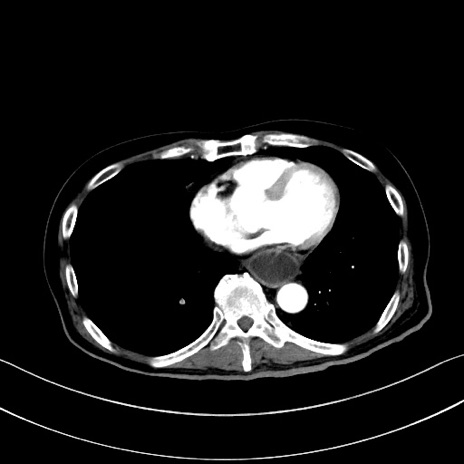

症例28(横断像)

【症例】60歳代男性

【主訴】嘔吐

【現病歴】胃癌にて胃全摘後。食思不振が悪化し、夜中に嘔吐することがある。

【既往歴】胃癌、胃全摘、脾摘、胆摘後

【データ】WBC 5900、CRP 10.56